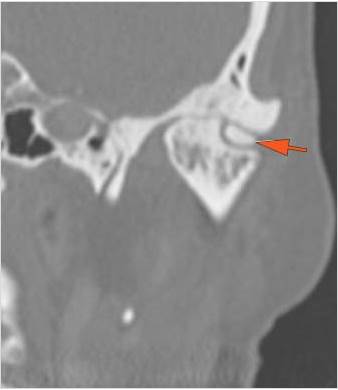

The condylar head and fossa as well as the temporomandibular joint space are abnormal. [Yes/No]

There is condylar fracture either within or outside of the joint capsule, or with or without involvement of the articular surface of the condylar head. [Yes/No]

There is evidence of radiodense intra-articular osteochondral fragments. [Yes/No]

There is bony injury or displacement of the external auditory canal and/or other evidence of temporal bone injury. [Yes/No]